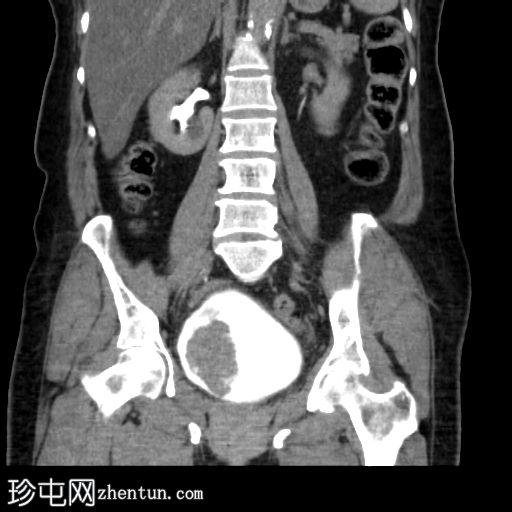

冠状位增强扫描

延迟期

5.jpg

膀胱内可见一边界清晰、不规则、可移动的软组织病变(CT值65 HU),直径约40 mm。病变无钙化,增强扫描后无强化。首要鉴别诊断为血肿。

采用俯卧位CT扫描显示病变活动度。

膀胱镜检查证实存在血肿,并进行了血块清除术。